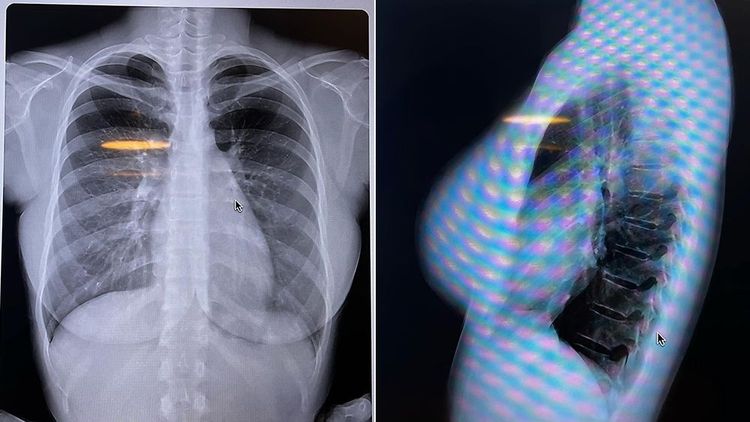

鈴木富美奈日前在推特發文表示,這是自己第一次向別人展示自己的骨骼和脂肪,「這樣就能證明我的胸部是天然的了吧」。並附上了自己正面和側面的胸部X光照片。

鈴木富美奈公布胸部X光照片。翻攝自鈴木富美奈推特